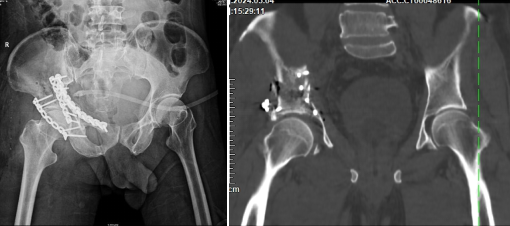

術后DR與CT顯示骨折復位固定好,關節面平整

手術期間,該院骨科團隊按照術前規劃,精準入路完成了良好的復位和固定,整個手術用時短,創傷小,出血量顯著減少,患者疼痛輕。術后復查顯示,關節面平整,頭臼關系匹配良好,且患者恢復迅速。